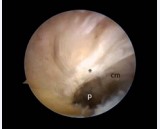

A 44 year old patient, male suffering from rheumatoid arthritis, complaining pain and clamping of the right knee for 5 years during the daily routine activities, with no associated trauma. The patient presents with a history of physiotherapy treatment and two arthroscopic procedures, with no improvement of symptoms. Radiographic examination revealed an image consistent with an intra-articular loose body in the medial compartment, in the topography of the posterior horn of the meniscus (Figure 1). The Magnetic Resonance Imaging (MRI) enabled the identification of bone tissue internal to the posterior horn of the medial meniscus (Figure 2). The surgical treatment was performed by arthroscopy via inter condylar access through the anterolateral and anteromedial portals (Figure 3) to position the optics and visualization of the posterior compartment (Figure 4). We identified the mensicalossicle adjacent to the posterior horn of the medial meniscus (Figure 5) and performed its removal utilizing basket forceps associated with economic resection of the posterior horn of the meniscus, due to the intimate anatomic relation between the two structures (Figures 6,7). The material was subjected to histopathological analysis, which identified fragments of meniscus containing hyaline alterations and metaplastic ossification, apart from a degenerative process, fibrosis, and foci of neovascularization (Figure 8). The patient evolved satisfactorily, with complete recovery of the range of motion and absence of joint locking symptoms, being that his last clinical evaluation was done with 3 months of postoperative. The last X-ray showed the absence of the bone body on the posterior compartment of the knee (Figure 9).

Figure 3: Arthroscopic image obtained with the optics in the anterolateral portal. The progress in the interval (p) between the fibers of the Posterior Cruciate Ligament (*) and the medial condyle (cm) confer access to the posterior region of the medial compartment.